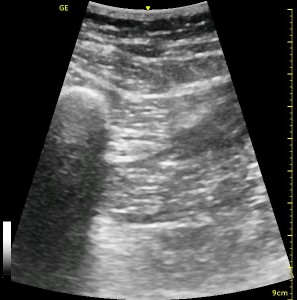

The following ultrasound image shows typical relationships of the sonoanatomy of the anterior sciatic nerve block. The femur is at 4cm on the right (lateral) of the image seen as a bright white horizontal line. Typically, there is a bone shadow below it, though there is some artifact below the femur here. The femoral vessels are seen between the 2cm and 3cm marks just to the right of center as a darkened area. They really can be determined by pausing for the appearance of arterial pulsation and venous compressibility. The adductors are seen to the left of the femur as a darkened area. Just deep to this between the 6cm and 7cm mark is a brightened rectangular shape, the sciatic nerve. The brightness fill fade with rocking of the probe over it. The nerve can be approached from the medial or lateral aspect of the probe, and moving the probe medially will sometimes allow for a better trajectory.

The image above is not an obvious one, and I did that on purpose. You have to get used to the idea that you will not always have a ‘super distinct’ image with this approach, and you will often need to use a number of additional clues to find your target and then to put local around it. I think the only way to really get a handle on being able to identify the basic elements is to look at several images over and over, so I have provided several below for you to use for practice. Note that the sciatic nerve will ‘poke out’ from behind the femur to different degrees depending on your orientation to the femur as well as to how far up or down the femur you go. It will be seen more if you are proximal. See how well you can identify the structures in the images below.